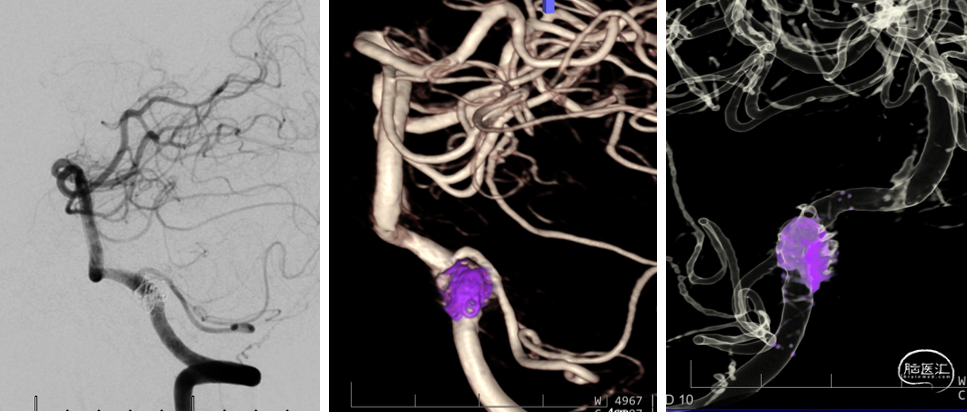

造影显示左侧椎动脉非优势侧

(5F造影导管即造成造影剂的滞留)

右侧椎动脉造影证实V4段夹层动脉瘤

(可见内膜瓣/瘤内造影剂滞留)

3D造影:动脉瘤处有明显的凹陷,符合夹层内膜瓣表现;PICA从动脉瘤远端发出,动脉瘤大小约6.5×12.8mm,受累椎动脉直径约4.3mm,覆盖远近端达正常血管约需30mm支架长度。